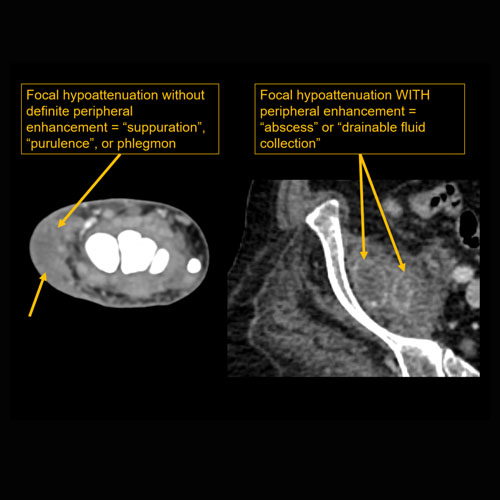

There is confluent hypoenhancement to suggest phlegmon, suppuration, abscess, or drainable fluid collection.

[Yes/No]